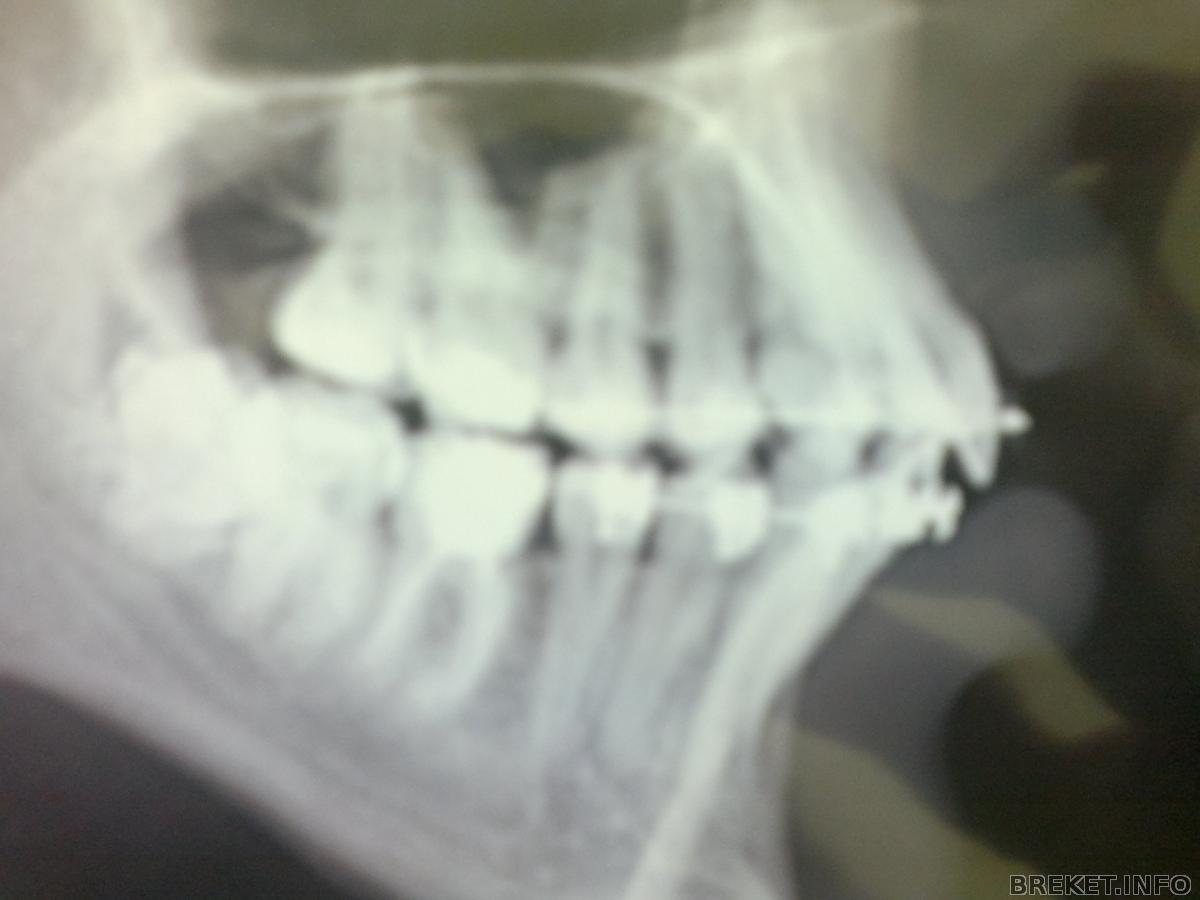

По своим новым "снимочккам" в БС, я определила

(глаз-алмаз) что за год с хвостом, ничего не изменилось

Ещё ближе